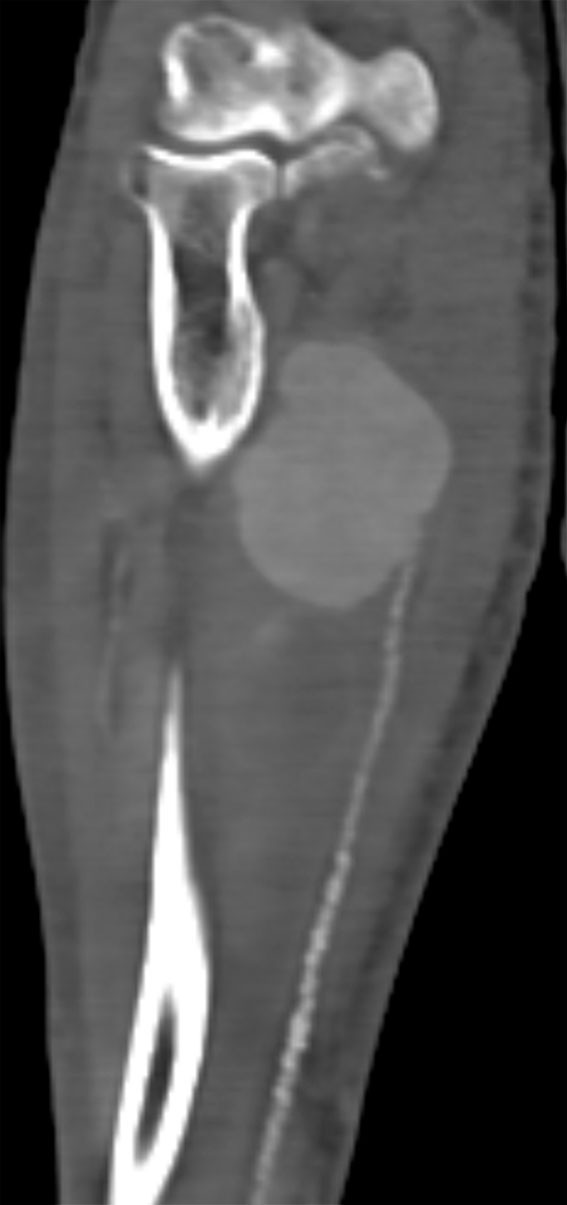

Tolv dager etter innleggelsen merket pasienten en smertefull hevelse i høyre underarm. Ultralyd viste en utposning på a. ulnaris. CT-angiografi tatt samme dag bekreftet ultralydfunnet og viste et aneurisme på 7,5 × 4 cm (figur 1). Det var rikelig med aterosklerotiske forandringer distalt for aneurismet. Ved klinisk undersøkelse var det god sirkulasjon til hånden ved avklemming av a. ulnaris.